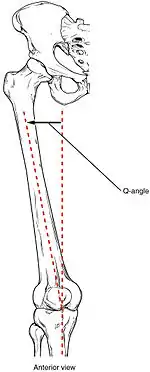

The degree of genu valgum can clinically be estimated by the Q angle, which is the angle formed by a line drawn from the anterior superior iliac spine through the center of the patella and a line drawn from the center of the patella to the center of the tibial tubercle. In women, the Q angle should be less than 22 degrees with the knee in extension and less than 9 degrees with the knee in 90 degrees of flexion. In men, the Q angle should be less than 18 degrees with the knee in extension and less than 8 degrees with the knee in 90 degrees of flexion. A typical Q angle is 12 degrees for men and 17 degrees for women.[6]